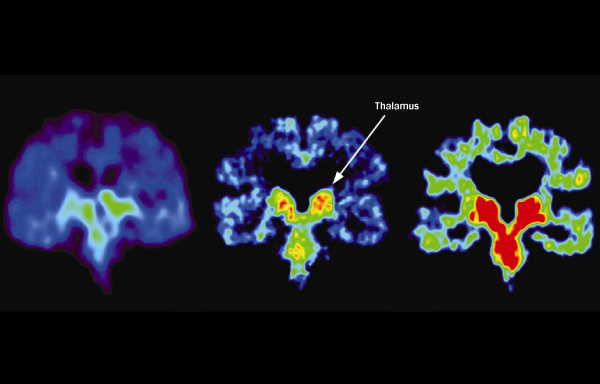

For the first time, scientists have seen the ravages of repeated concussions in the brains of living people. Brain scans of five retired National Football League players reveal unusual deposits of an ominous protein called tau that used to be identifiable only through autopsy. Tau is a hallmark of chronic traumatic encephalopathy, a disease that causes the gradual appearance of mental and emotional problems in people who have experienced repeated brain trauma.